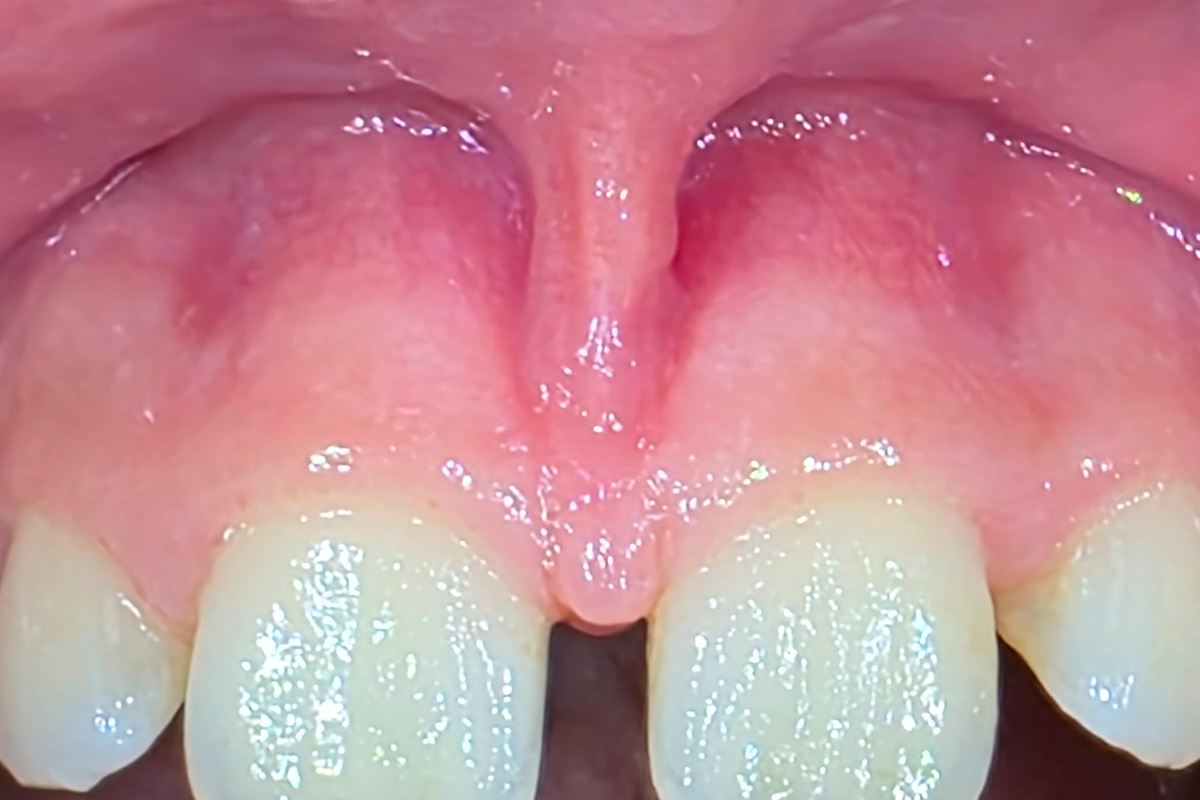

FRENECTOMIE LABIALE